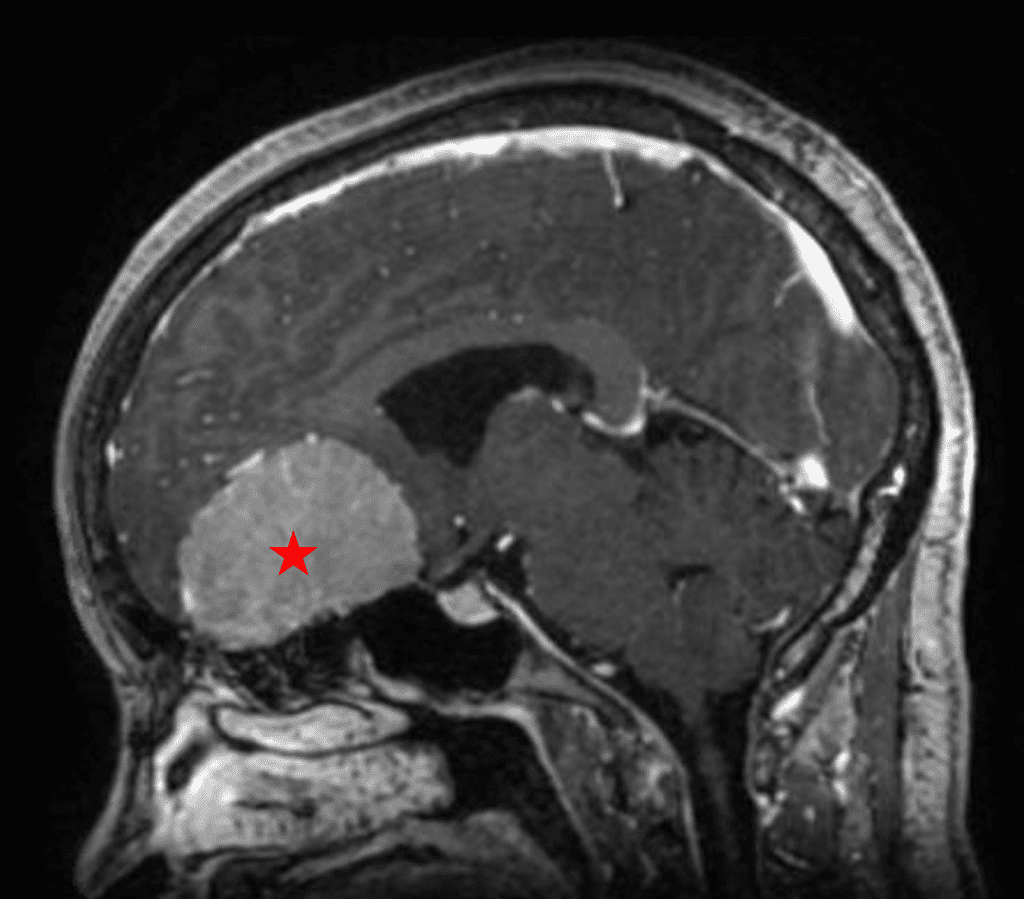

Figure 1b – Postoperative MRI demonstrating a complete resection without residual enhancement.

She was started on high-dose steroid and antiseizure prophylactic medicine. Surgical intervention was offered for mass effect, symptomatic relief, neurologic preservation, and histopathologic diagnosis. Dr. Gaudin performed a bifrontal craniotomy with complete resection of neoplasm through an interhemispheric and subfrontal approach. Postoperative imaging demonstrated a gross total resection without residual tumor and resolution of mass effect (Figure 1b and 2b). Intraoperative pathology was consistent with meningioma, WHO grade 1. She recovered very well, and was discharged home on postoperative day 3. On her follow-up outpatient visit, her preoperative symptoms had fully resolved, and her olfactory sense was maintained.

Figure 2b – Postoperative MRI demonstrating resolution of mass effect.